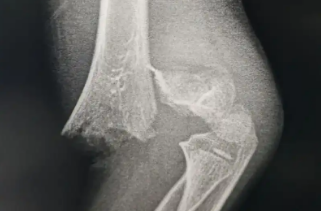

这几天,北京、武汉、南京、合肥等地普降大雪,因路面湿滑导致滑倒摔伤人群增加,不少医院里骨科、急诊接诊人数持续增加。北京大学第一医院骨科常务副主任孙浩林说,因雨雪天摔倒就诊的患者伤情多集中于手腕、髋骨和踝关节骨折,尤其是一些老年患者因骨质疏松,摔伤后需及时接受进一步治疗。

万一摔倒了,哪些情况可能是骨折了?公茂琪提示,在摔倒情况下,不要立即站起,应该先确认自己的肢体是否能够正常活动,身体躯干是否出现严重的疼痛,四肢是否发生严重的翻转、肿胀,及时就诊:

首都医科大学附属北京积水潭医院创伤骨科主任 公茂琪:一般讲究“先固定再搬运快就医”,你别移动受伤的部位,也别揉搓、推拉,因为会加重骨折的移位,甚至严重的骨折(很锐利的情况下)会损伤周围的神经血管,要求快速的固定,身边有什么就借用什么,譬如你带着书本,甚至什么都没有把围巾缠一缠轻轻地固定这个受伤部位,手指头能伸进去一个手指就可以了,然后赶快拨打120;譬如说要是胯骨骨折了,因为是比较严重的,就不要大动了,让病人就是平躺在担架上,也别让病人再起身翻身的,到了医院里,根据这个情况由医生来处理,是比较适宜的。